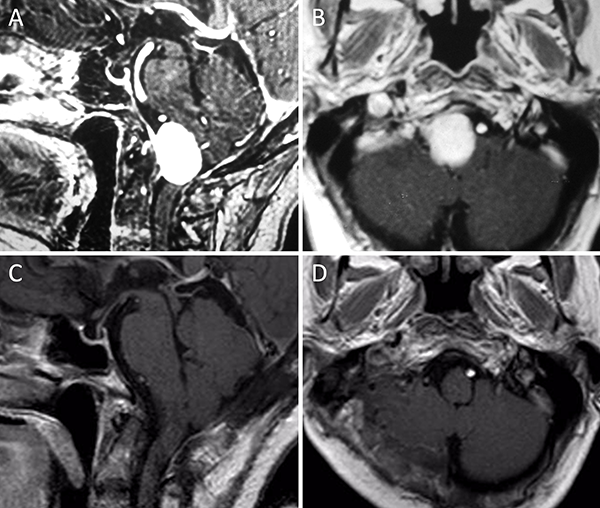

Figura 1. Meningioma tentorial medial. A-B: RM preoperatoria; C-D: RM postoperatoria.

Figura 2. Meningioma tentorial lateral. A-B: RM preoperatoria; C-D: RM postoperatoria.